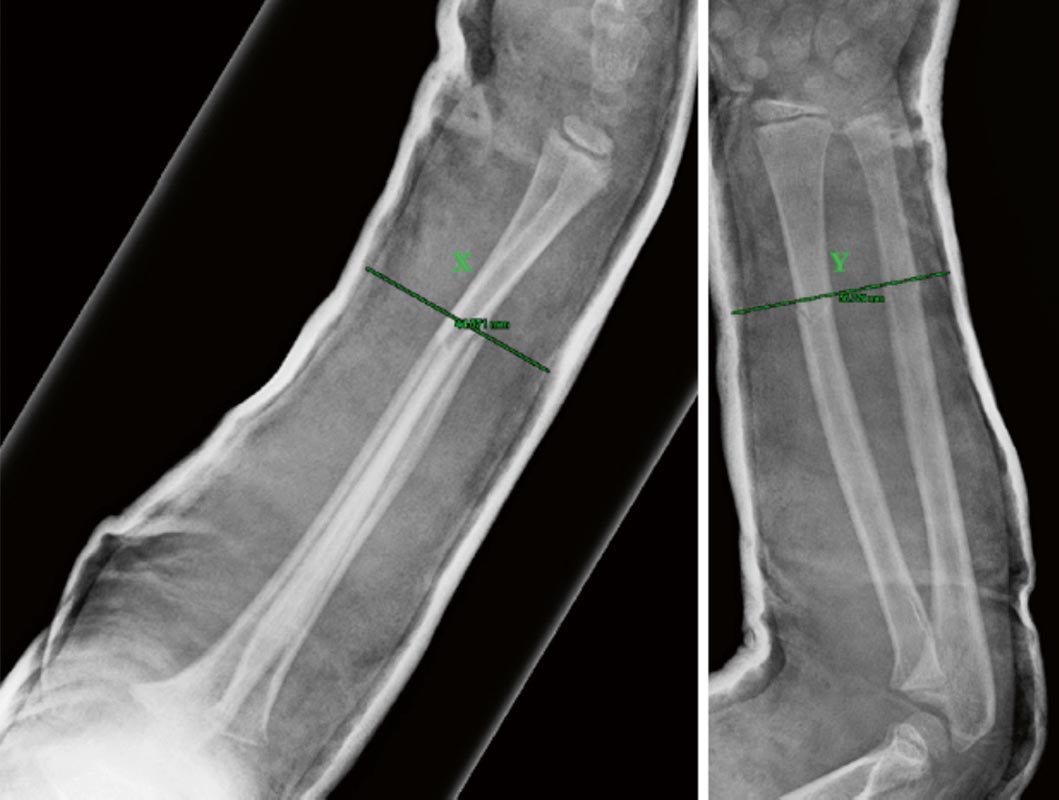

Il trattamento chirurgico mira a una stabilizzazione efficace con minimo danno ai tessuti molli, per mantenere un’adeguata riduzione fino a completa consolidazione della frattura. Il trattamento chirurgico più comune è la sintesi endomidollare elastica (ESIN). Il trattamento chirurgico con ESIN, che ha visto espandere le sue indicazioni e la sua applicazione negli ultimi 30 anni, nonostante i buoni risultati complessivi che fornisce va comunque limitato alle corrette indicazioni: fratture instabili o potenzialmente instabili, fratture in adolescenti oltre i 12 anni dove il rimodellamento prevedibile è limitato, fratture esposte, alto rischio di sindrome compartimentale, rifratture. La tecnica ESIN prevede l’applicazione di chiodi endomidollari elastici in grado di mantenere la riduzione sfruttando la pressione su diversi punti del canale endomidollare. Il planning prevede l’utilizzo di un chiodo per il radio e uno per l’ulna. L’impianto nel radio avviene sempre per via retrograda dalla metafisi distale, mentre per l’ulna si accede dalla faccia laterale o mediale della metafisi prossimale o dalla metafisi distale a seconda della sede di frattura 10. Per l’accesso dalla metafisi distale del radio sono state descritte due modalità: l’accesso dalla faccia laterale della metafisi radiale oppure l’accesso dalla faccia dorsale della metafisi, a livello del tubercolo di Lister. Entrambi gli accessi richiedono grande premura nei confronti del ramo sensitivo dorsale del nervo radiale e del tendine estensore lungo del pollice. In entrambi i casi è consigliato eseguire una piccola incisione cutanea seguita da accurata dissezione dei piani profondi fino alla superficie ossea, in modo da individuare e proteggere le suddette strutture anatomiche. Non esistono evidenze su quale sia il segmento osseo da trattare per primo: solitamente viene trattato prima il radio in quanto risulta essere il segmento più difficile da ridurre. Si consiglia di scegliere un chiodo di diametro pari a 2/3 del canale diafisario, misurato al suo terzo medio. La procedura permette la riduzione e la stabilizzazione della frattura con due piccoli accessi cutanei, rispettando al massimo i tessuti molli e il focolaio di frattura. Al termine dell’intervento le code dei chiodi vengono tagliate vicino al piano osseo e lasciate sottopelle. Lasciare i chiodi fuori dalla pelle permette la loro rimozione ambulatoriale ma può esporre al rischio di infezione, rallentando il recupero funzionale.

Altri sistemi di sintesi utilizzati i fili di Kirschner, i fissatori esterni e le placche. L’utilizzo dei fili di Kirschner trova ancora la sua indicazione nelle fratture del terzo distale della diafisi, al limite con le fratture metafisarie, dove l’applicazione degli ESIN risulta poco agevole e fonte di possibili perdite di riduzione secondarie. La fissazione esterna riveste un ruolo maggiore nelle fratture esposte. Le placche, utilizzate a cielo aperto come nell’adulto, sono destinate al trattamento degli esiti. Nella maggior parte dei casi non è necessario un lungo periodo di immobilizzazione dopo l’intervento, anzi, alcuni autori incoraggiano la mobilizzazione attiva e passiva precoce. I controlli RX vengono eseguiti a quattro settimane e a tre mesi dalla frattura. La rimozione dei chiodi può essere pianificata in un tempo variabile tra i 6 e i 18 mesi dalla frattura.